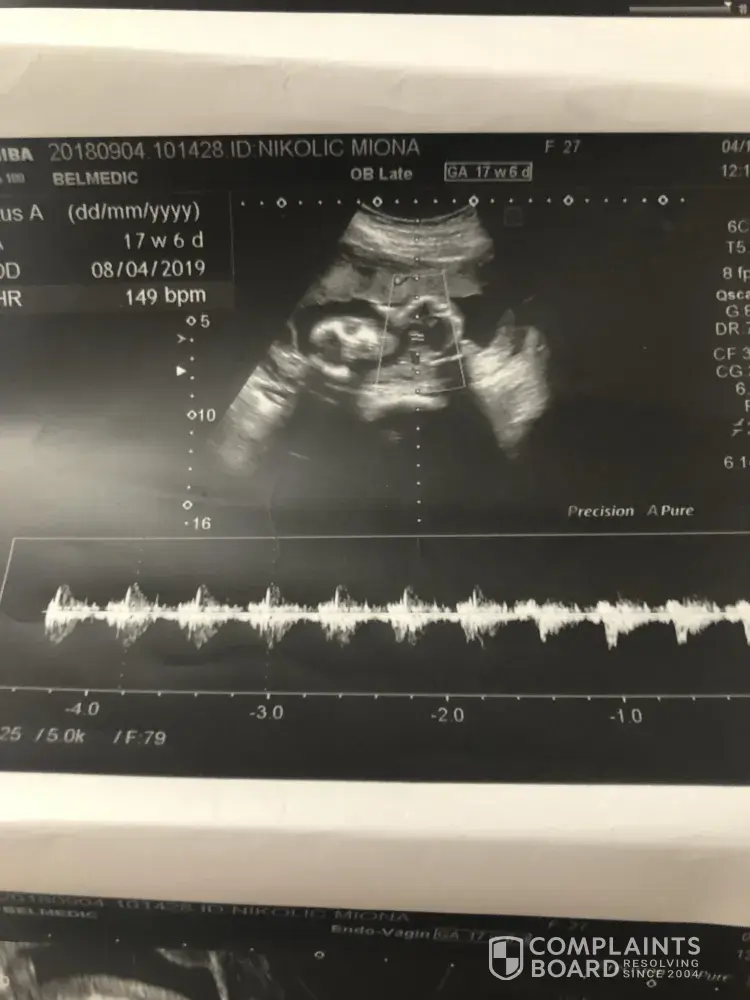

I was traveling from Bahrain-Abu Dhabi-Belgrade on 2nd of November. My flight from Bahrain was supposed to depart at 10:45 pm but it was late and I didnt make it on time for my flight Abu Dhabi-Belgrade at 2:15 am. Instead they gave me a ticket for Athens at 9:15 am and there I had to wait for 4 hours before my flight to Belgrade. I had more then 7 hours to wait at Abu Dhabi airport, I am 5 months pregnant and I had to pay for a hotel at the airport ( I'm sending you a receipt).

I am asking you to recompense my loss by giving me refund in the amount of the return ticket i paid for my flight Belgrade-Abu Dhabi-Bahrain.

My name is Miona Nikolic, my passport number is [protected], number of my bank account is [protected] at Telenor bank, Serbia.